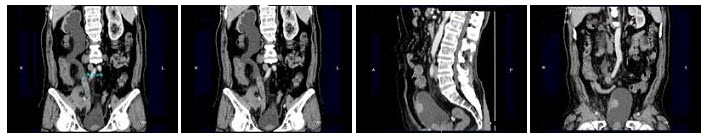

9、多项选择题

男,20岁,右腰部胀痛不适,MRI如图示,下列说法正确的是()

A.右侧肾盂积水

B.右侧输尿管上段扩张积水

C.右侧输尿管走行异常,呈“S”形向中线移位

D.考虑为右侧腔静脉后输尿管

E.考虑为右侧输尿管自身的扭曲